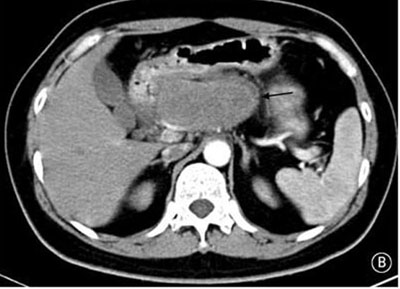

就診時(shí)實(shí)驗(yàn)室檢查結(jié)果顯示嚴(yán)重高血糖(血糖水平為982mg/dL[55mmol/L])。腹部CT檢查顯示胰頭部位出現(xiàn)一個(gè)9cm大小的腫塊(如圖B箭頭所示)。空腹血清胰高血糖素水平為530pg/ml(正常值≤80pg/ml)。